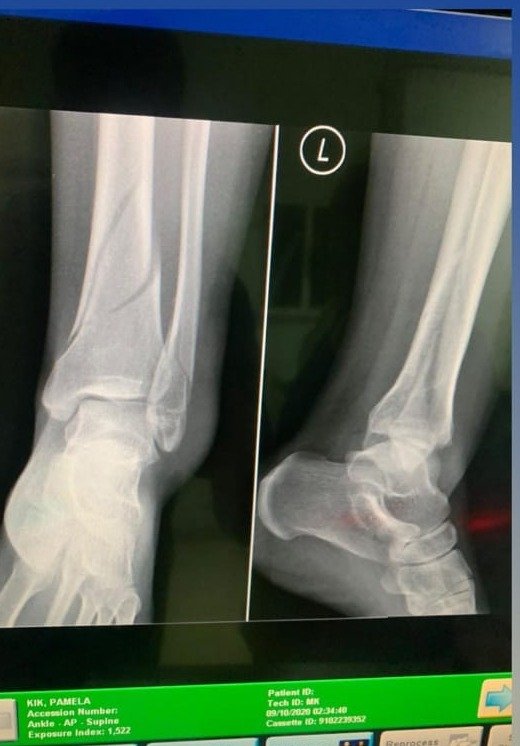

نشرت الممثلة اللبنانية باميلا الكيك عبر حسابها الرسمي على إنستغرام، مقطع فيديو أعلنت خلاله عن إصابتها بكسرين في قدمها ورضوض في الأخرى ما يحول دون قدرتها على السير لما يقارب الشهر ونصف الشهر. وفي التفاصيل، ظهرت الممثلة باميلا الكيك في الفيديو الذي نشرته وهي ترتدي ثياب المستشفى.

إذ عمدت الى طمأنة جمهورها بأنها لا تعاني من فيروس كورونا، بل قامت بخطوات خاطئة أثناء السير أدت إلى اختلال توازنها، وتعرضها لكسرين في قدمها ورضوض في الأخرى ما يفرض عليها التزام السرير، لتستعيد قدرتها على السير بطريقة طبيعية وممارسة حياتها الطبيعية.